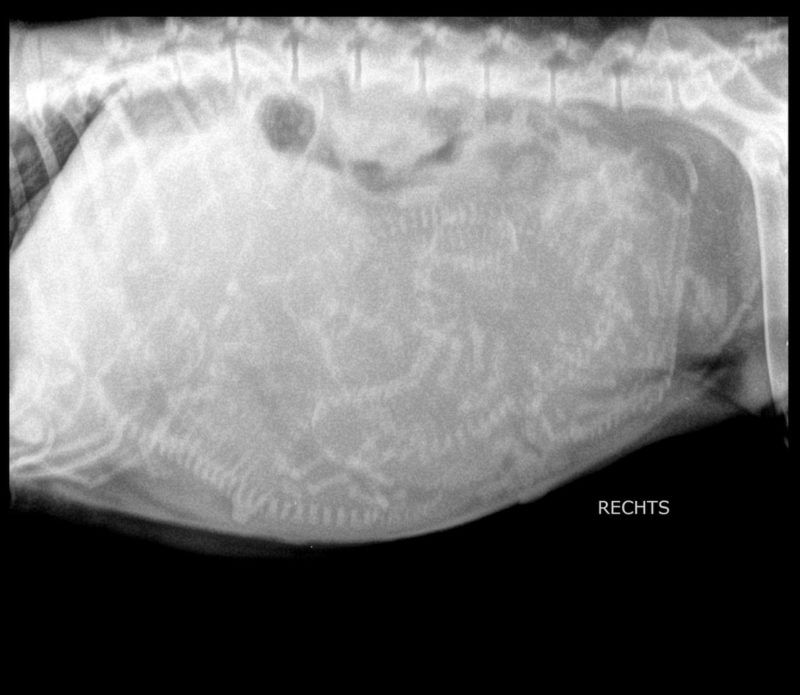

Die Untersuchungen Nalas per Ultraschall und Röntgen ergaben keine pathologischen (krankhaften) Befunde. Bei der Blutuntersuchung wurden eine leichte Anämie (Blutarmut) und ein deutlicher Hinweis auf eine bakterielle Infektion festgestellt. Nach entsprechender medikamenteller Behandlung mit Dauertropfinfusion wurde ein Welpe geboren. Trotz sich anschließender Arzneimittelgaben konnte keine weitere Spontangeburt ausgelöst werden.

In Absprache mit den Besitzern entschied ich mich für einen Kaiserschnitt, um eine gute Überlebenschance der noch nicht geborenen Welpen zu erhalten. Aufgrund der fortgeschrittenen Zeit, mittlerweile war es Mitternacht, und der Notbesetzung des OP-Teams wurden die Tierbesitzer in die Versorgung der Welpen mit einbezogen. Umgehend war Nala für die Operation vorbereitet und narkotisiert. Fünf weitere Welpen konnten lebend entwickelt werden. Leider waren zwei Welpen bereits im Mutterleib verstorben.